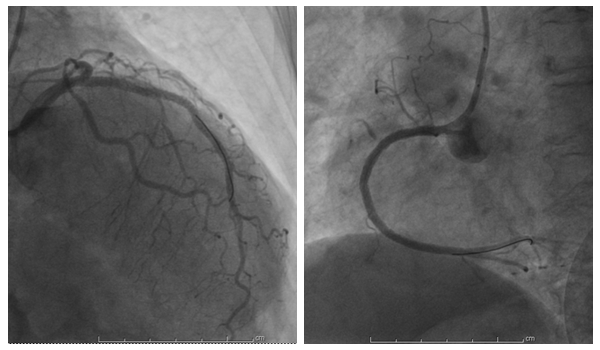

储奶奶术前冠脉血管病变

64岁储奶奶,反复出现胸闷、气促6年,伴剑突下灼烧感(肚子发烫感),视物模糊。2年前于某三甲医院诊断“严重冠心病”,冠脉造影示:冠脉血管三支病变,(左前降支:前降支近中段钙化病变,近中段弥漫性狭,最95%,左回旋支:全程钙化病变,近段局限性狭窄25%,中段弥漫性狭窄50%-80%,右冠状动脉:开口局限性狭窄50%,近-中段钙化病变弥漫性狭窄70%-99%,右室支粗大,开口局限性狭窄99%.),介入手术难度大,建议早期完善血管再通手术。时间一天天过去,病情发病的频率越来越多,患者拒绝手术,反复就诊全国多家医院药物治疗无效。日常生活质量差,家务活做不了,足不出户,不愿意出去散步,甚至吃饭心绞痛也可发作,整天沉浸在病痛中,身体日渐消瘦,内心逐渐变得焦虑及敏感。2019.08.19带着期待来到湘雅常德医院心内科住院,彭道地主任及范爱德副主任医师多次强调:冠脉介入治疗手术风险极大,由于血管长期未开通,血管钙化重,在手术中存在血管破裂或者血管难以开通可能性大,建议早期行胸外冠脉搭桥手术改善心肌供血。患者及家属言辞拒绝开胸冠脉搭桥术,特别强调要尝试心脏血管介入开通治疗,愿意承担一切后果予以生死一搏。

储奶奶术后血管通畅